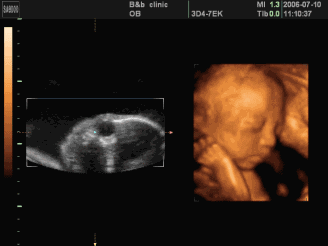

这个小宝宝好安静

以后肯定是个懂事的好baby!